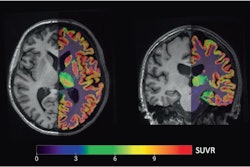

In preclinical work, PET imaging using a radiotracer named F-18 FET has been shown to bind with high affinity to a molecular target in pituitary tumors, and in this study, the researchers aimed to test this technique combined with MRI in a multimodal approach.

The researchers analyzed results from 22 patients (68% women; mean age 48 years) who underwent F-18 FET PET/MRI at Erasmus MC between February 2021 and December 2022. All patients showed a clear pituitary tumor F-18 FET-PET/MRI, whereas reading of the MRI alone yielded a suspected lesion in only 50%, the authors found.